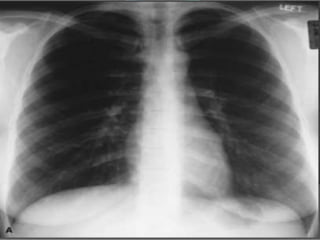

Atelectasia

• Hipertransparência (um

hemitórax; toda área

pulmonar; pequenas

áreas);

• Colapso Alveolar;

• Diminuição dos espaços

intercostais;

• Desvio do mediastino

ipsilateral;

• Elevação da hemicúpula

diafragmática (se for em

base).

Atelectasia • Hipertransparência (um hemitórax;toda área pulmonar; pequenas áreas); • Colapso Alveolar; • Diminuição dos espaços intercostais; • Desvio do mediastino ipsilateral; • Elevação da hemicúpula diafragmática (se for em base).